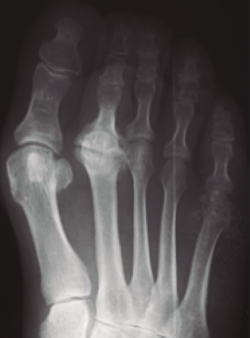

Figura 5. Tratamiento conservador. Paciente tratada con plantilla de descarga. A: imágenes al inicio del tratamiento; B: 2 años más tarde, mínima afectación articular.

En las fases iniciales (estadios 1 y 2 de Smillie) en las que, tal como se ha comentado, las molestias del paciente son inexistentes o leves, están indicadas las plantillas ortopédicas de descarga de la cabeza metatarsal afecta, los antiinflamatorios no esteroideos (AINE) y la electroterapia antiinflamatoria durante la crisis de dolor. Se recomienda al paciente disminuir la práctica deportiva de impacto(11,17). Con ello se consigue que, cuando se finaliza la fase de reparación, la deformidad sea la menor posible (Figura 5).